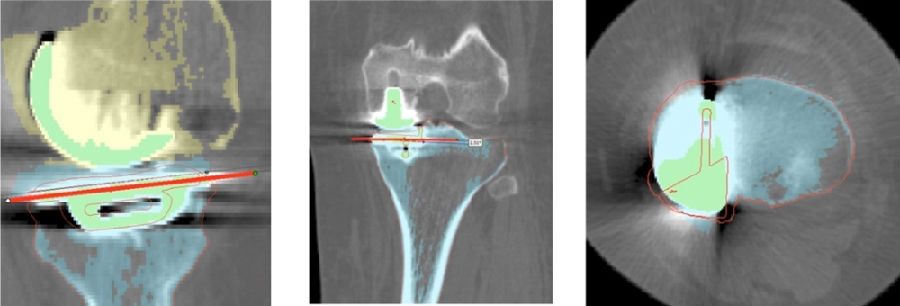

术前确认方案,包括大小型号,冠状矢状以及轴面上不同位置,如何选择每个人比较合适的假体相关位置。

术前确认方案

同时,笔者团队也在和导板公司进行合作,把用术后CT和术前CT进行匹配,来验证术前规划的偏离度有多少,包括胫骨后倾、冠状面内倾、轴面胫骨假体旋转、股骨在冠状面的角度、股骨在轴面上的旋转角度以及在矢状面上屈伸角度。

符合度验证

简单总结一下近期的数据,共20例患者的20例膝关节,男5人(25%),女15人(75%),左膝11例(55%),右膝9例(45%)。平均年龄69.8+5.6岁。以±3°作为整个导板设计规划与实际实施的幅度标准。术前规划与术后实际型号没有任何区别,是100%的符合度。

胫骨后倾角有95%的符合度,胫骨内翻角是100%的符合度;胫骨旋转仍然存在一个相对大的差距,但是比传统工具要更好,有70%的病人胫骨内旋角是在范围之内。

股骨在冠状面的角度上也是比较好的表现,股骨内翻角存在95%的符合度,股骨内外旋转角稍差一点,但也达到70%。目前唯一还存在不太满意的地方就是矢状面上股骨假体低头,这个角度偏差度和术前规划差距较大,有50%的准确。